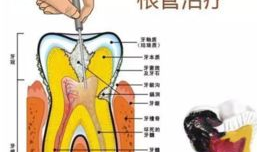

根管治疗视频,从视频学习根管治疗技巧与流程

最近是不是牙齿疼得你坐立不安,连笑容都变得苦涩了呢?别担心,今天就来给你揭秘一下那个听起来有点吓人的根管治疗,让你对这个过程有个...

2025-09-01 273 -